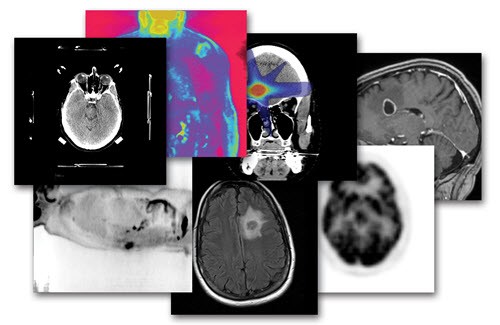

Servicio disponible para diversas combinaciones de imágenes de:

Tomografía

Resonancia Magnética

PET-CT

Con la finalidad de mejorar la precisión al máximo de los tratamientos de radioterapia, somos capaces de integrar los estudios de imagen del paciente, incluyendo tomografías contrastadas, resonancia magnética e incluso el moderno PET-CT, mediante poderosos programas de cómputo especializado, que fusionan estas imágenes en un solo plan maestro integral.